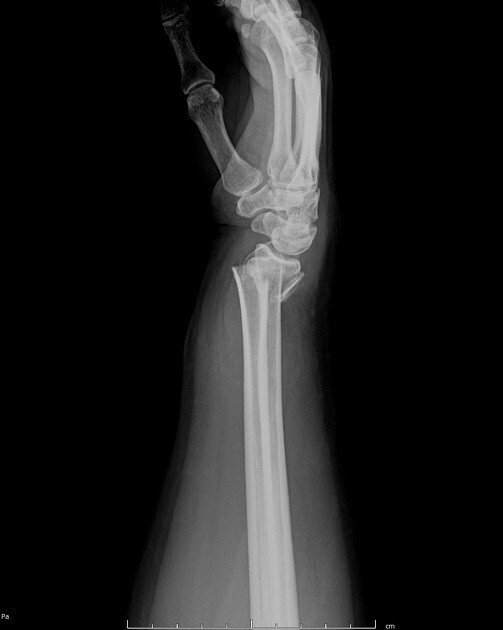

Dinner Fork Arm Fracture . If dorsal angulation is severe enough, a. The clinical presentation of colles fracture is commonly described as a dinner fork deformity. A dinner fork deformity, also known as a bayonet deformity, occurs as the result of a malunited distal radial fracture, usually a colles. Identify the etiology and epidemiology of colles fractures. Outline the appropriate history, physical, and evaluation of a patient with a colles fracture. Dorsal angulation of the distal fracture fragment is present to a variable degree (as opposed to volar angulation of a smith fracture). A distal fracture of the radius causes posterior displacement of the distal fragment, causing. Deformity of the wrist, sometimes called a “dinner fork deformity,” which causes it to look crooked and bent.

Smith Fracture Distal Radial Fracture Radiology Case RadioGyan Dinner Fork Arm Fracture Deformity of the wrist, sometimes called a “dinner fork deformity,” which causes it to look crooked and bent. A dinner fork deformity, also known as a bayonet deformity, occurs as the result of a malunited distal radial fracture, usually a colles. Identify the etiology and epidemiology of colles fractures. The clinical presentation of colles fracture is commonly described as a. Dinner Fork Arm Fracture.